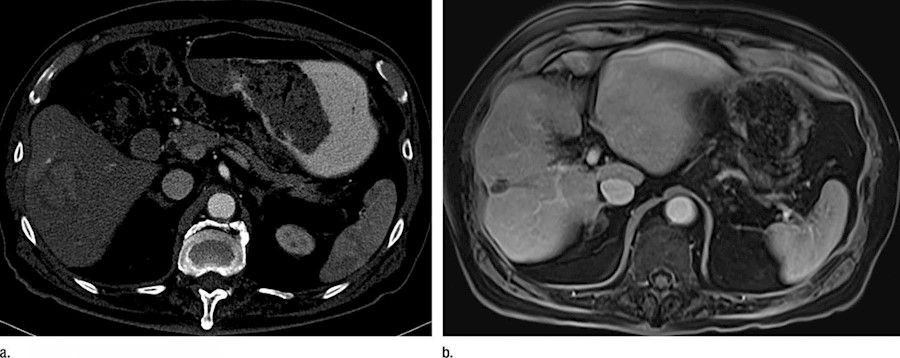

Un primer ensayo clínico en humanos demuestra una mejora en el tratamiento con radiación del cáncer de hígado

Una nueva investigación ha demostrado, a través del primer ensayo clínico en humanos, que el actual tratamiento del cáncer del hígado mediante radioterapia dirigida administrada con la ayuda de perlas de vidrio que emiten radiación se puede aumentar al infundir microburbujas (pequeñas burbujas de gas rodeadas por una capa de lípidos) en el hígado y hacer estallar esas burbujas por ultrasonido, según publican los investigadores en la revista `Radiology`.

Alrededor del 15-25% de los pacientes con enfermedad avanzada se les recomienda un tratamiento llamado radioembolización transarterial, mediante el cual se insertan perlas de vidrio radiactivo en los vasos sanguíneos del hígado, y la radiación emitida proporciona una dosis terapéutica al tumor, destruyéndolo.

Sin embargo, la medida en que la radiación puede penetrar en el tejido hepático es limitada y la respuesta del tumor depende en gran medida de la distancia a las perlas radiactivas. Al combinar microburbujas con TARE, el enfoque sinérgico reduce la dosis de radiación necesaria para destruir los vasos sanguíneos del tumor y aumenta la eficacia del tratamiento.